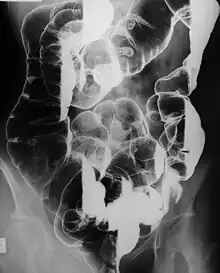

Manifestations of Peutz–Jeghers syndrome[1] | |

Peutz–Jeghers syndrome (often abbreviated PJS) is an autosomal dominant genetic disorder characterized by the development of benign hamartomatous polyps in the gastrointestinal tract and hyperpigmented macules on the lips and oral mucosa (melanosis).[2] This syndrome can be classed as one of various hereditary intestinal polyposis syndromes[3] and one of various hamartomatous polyposis syndromes.[4] It has an incidence of approximately 1 in 25,000 to 300,000 births.[5]

- Hamartomatous polyps in the gastrointestinal tract. These are benign polyps with an extraordinarily low potential for malignancy.